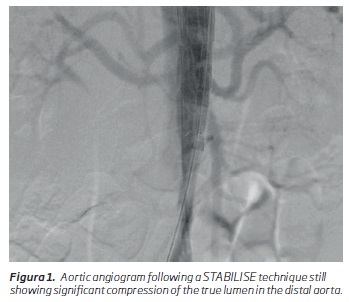

Regarding any surgical technique, patient selection is paramount. There is a small niche of patients in which a combination of the STABILISE and CERAB techniques may be applied. We can consider them a subgroup of the patients that have an indication for TEVAR and STABILISE. In the management of TBADs, first, a decision has to be made if the patient warrants treatment, and if he is applicable for a TEVAR. If the TEVAR is performed and there is still false lumen perfusion and true lumen compression distally in the control angiogram following the endograft placement, an extension using the STABILISE technique may be used. In these patients, if there are still signs of infra-renal aortic or iliac compression/occlusion or distal thrombosis of the false lumen (Figure 1), a CERAB may be performed in order to expand the true lumen and occlude these distal communicating tears.

After all the stents have been ballooned, an angiogram is performed to evaluate the distal aorta. If there are signs of true lumen compression with aortic/iliac compression/occlusion or distal false lumen thrombosis (Figure 1), a CERAB technique is performed.